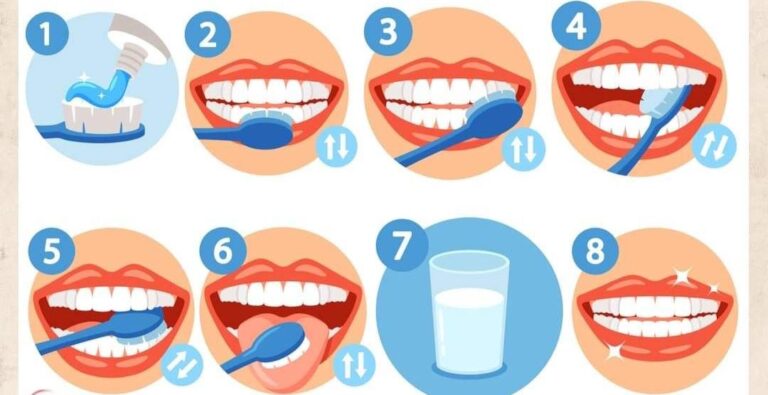

بهداشت دهان و دندان یکی از مهمترین بخشهای مراقبتهای روزانه است که تأثیر مستقیم بر سلامت عمومی بد…